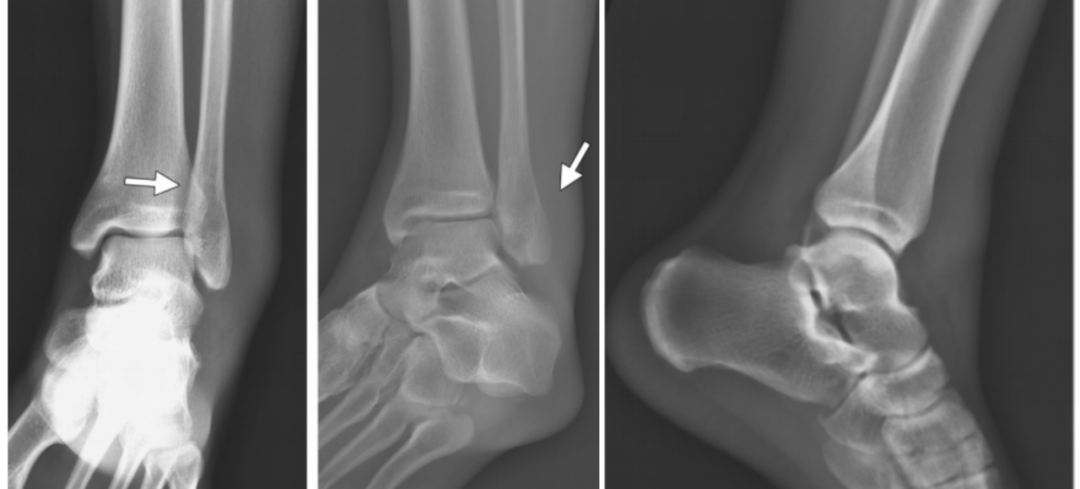

4、旋前(外翻)外展损伤(简称 PA)

伤足处于旋前位,而距骨是外展,三角韧带处于紧张,分为三度:

旋前外展损伤

Ⅰ 度:首先发生的是内侧三角韧带断裂或者内踝的撕脱骨折。

I 度损伤 X 线显示:内踝水平骨折;侧位片腓骨无骨折。

Ⅱ 度:距骨外展的力量继续作用于下胫腓关节,导致下胫腓前、后韧带的断裂或者撕脱骨折 ,骨间韧带、骨间膜撕裂。

II 度损伤 X 线片显示:腓骨无骨折,内踝间隙变宽,提示三角韧带断裂;侧位片显示后踝骨折(箭头)。

Ⅲ 度:距骨外展的力量作用于腓骨,使其外侧受到压力,内侧受到张力,导致腓骨在胫骨关节面附近发生短斜形骨折,主要骨折线基本呈横行,常伴有三角形小骨片,或者外部粉碎型的骨折;甚至可以伴有胫骨远端关节面外侧部分的压缩骨折。

III度损伤X线片显示:内踝间隙增宽,提示三角韧带断裂,胫腓骨间隙增宽,提示下胫腓联合断裂;腓骨斜向骨折,外侧高,内侧低;侧位片显示后踝骨折(箭头)。